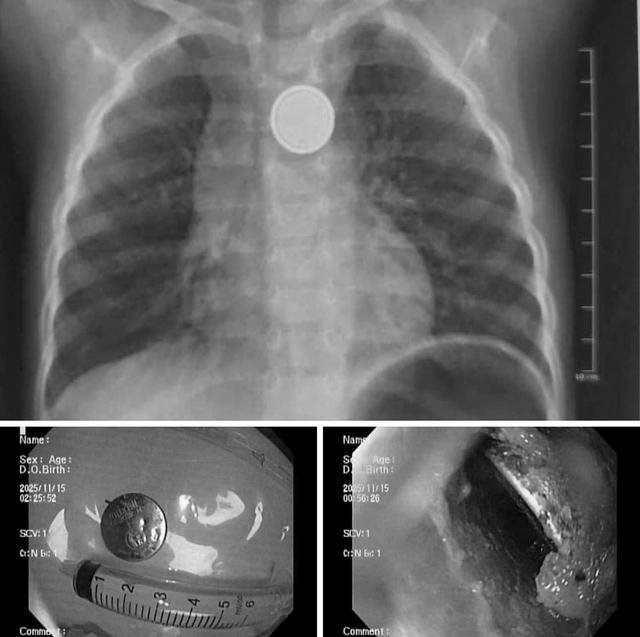

Bệnh nhi là bé trai 32 tháng tuổi được gia đình đưa đến viện ngay sau khi phát hiện đã nuốt phải viên pin cúc đồ chơi. Rất may, gia đình phát hiện sớm và đưa trẻ đến bệnh viện trong khoảng 1 giờ sau khi nuốt.

Tại bệnh viện, các bác sĩ đã tiến hành chụp X-quang, kết quả cho thấy dị vật kẹt tại thực quản.

Hình ảnh dị vật là pin cúc áo trong thực quản trẻ.

Ê-kíp nội soi cấp cứu đã nhanh chóng tiến hành gắp thành công viên pin ra ngoài. Dù được cấp cứu sớm song qua quan sát trực tiếp, e-kip nội soi ghi nhận có vùng ăn mòn, gây loét thực quản.

Các bác sĩ cho biết, pin cúc đồ chơi có thể gây tổn thương nghiêm trọng chỉ trong thời gian rất ngắn. Do đó, việc lấy dị vật kịp thời giúp hạn chế nguy cơ thủng thực quản, nhiễm trùng trung thất và các biến chứng nặng khác.